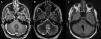

El tumor glioneuronal formador de rosetas del IV ventrículo es un tumor primario del sistema nervioso central introducido en el grupo de tumores glioneuronales en la clasificación de la OMS de 2007. Inicialmente se describió alrededor del IV ventrículo, pero recientemente se han publicados casos en distintas localizaciones. Presentamos 2casos de este raro tumor, ambos tratados quirúrgicamente. El primero en un varón de 41 años de edad, con síntomas típicos de lesión de fosa posterior; el segundo, en una mujer de 18 años de edad, con hallazgo incidental de lesión en fosa posterior que también fue tratada quirúrgicamente. Presentamos imágenes de resonancia magnética pre- y posquirúrgicas, aportamos imágenes histológicas de este tumor y realizamos una revisión de la literatura.

Rosette-forming glioneuronal tumor of the fourth ventricle is a primary central nervous system tumor introduced in the group of glioneuronal tumors in the WHO classification of 2007. Initially it was described around the fourth ventricle, but recently have been published cases in different locations.

We present 2cases of this rare tumor, both surgically treated. The first in a 41 year old man with typical symptoms of posterior fossa injury. The second in an 18 year old woman, with incidental finding of posterior fossa injury that was also surgically treated.

We present pre- and post-surgical magnetic resonance images, histological pictures of this tumor and we make a review of the literature.